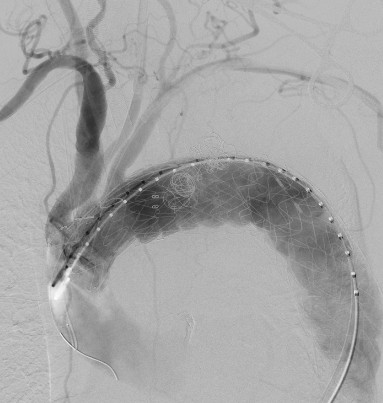

胸主動(dòng)脈支架原位開窗,有條不紊

(體外開窗)TEVAR手術(shù)緊張有序進(jìn)行中

穿刺股動(dòng)脈、切開頸動(dòng)脈、肱動(dòng)脈建立入路,超選內(nèi)漏口、栓塞瘤腔,體外預(yù)開窗、重建弓上動(dòng)脈......血管外科兩組人馬同時(shí)開工,有條不紊。在麻醉科林芩主任團(tuán)隊(duì)的密切配合下,一系列步驟緊張有序地進(jìn)行著。手術(shù)持續(xù)了4個(gè)多小時(shí),當(dāng)最終的造影確認(rèn)內(nèi)漏完全封閉、假性動(dòng)脈瘤成功隔絕,并且主動(dòng)脈弓上的重要分支動(dòng)脈血供良好的那一刻,血管外科團(tuán)隊(duì)成員都已忘卻了身上幾十斤的鉛衣和滿身的汗水。夏印主任和黎成金主任不禁對(duì)視一笑:“拆雷成功,又救了一條命?!?

瘤腔及內(nèi)漏成功封堵,弓上分支動(dòng)脈血流通暢